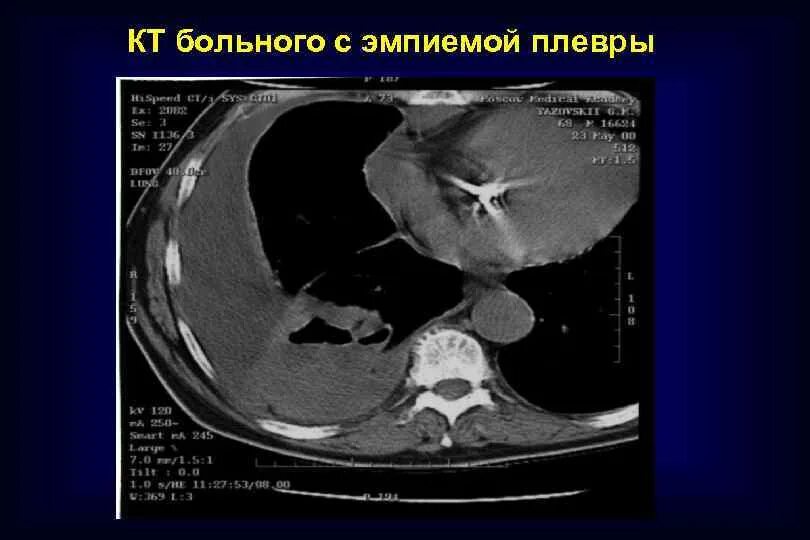

Болит кт